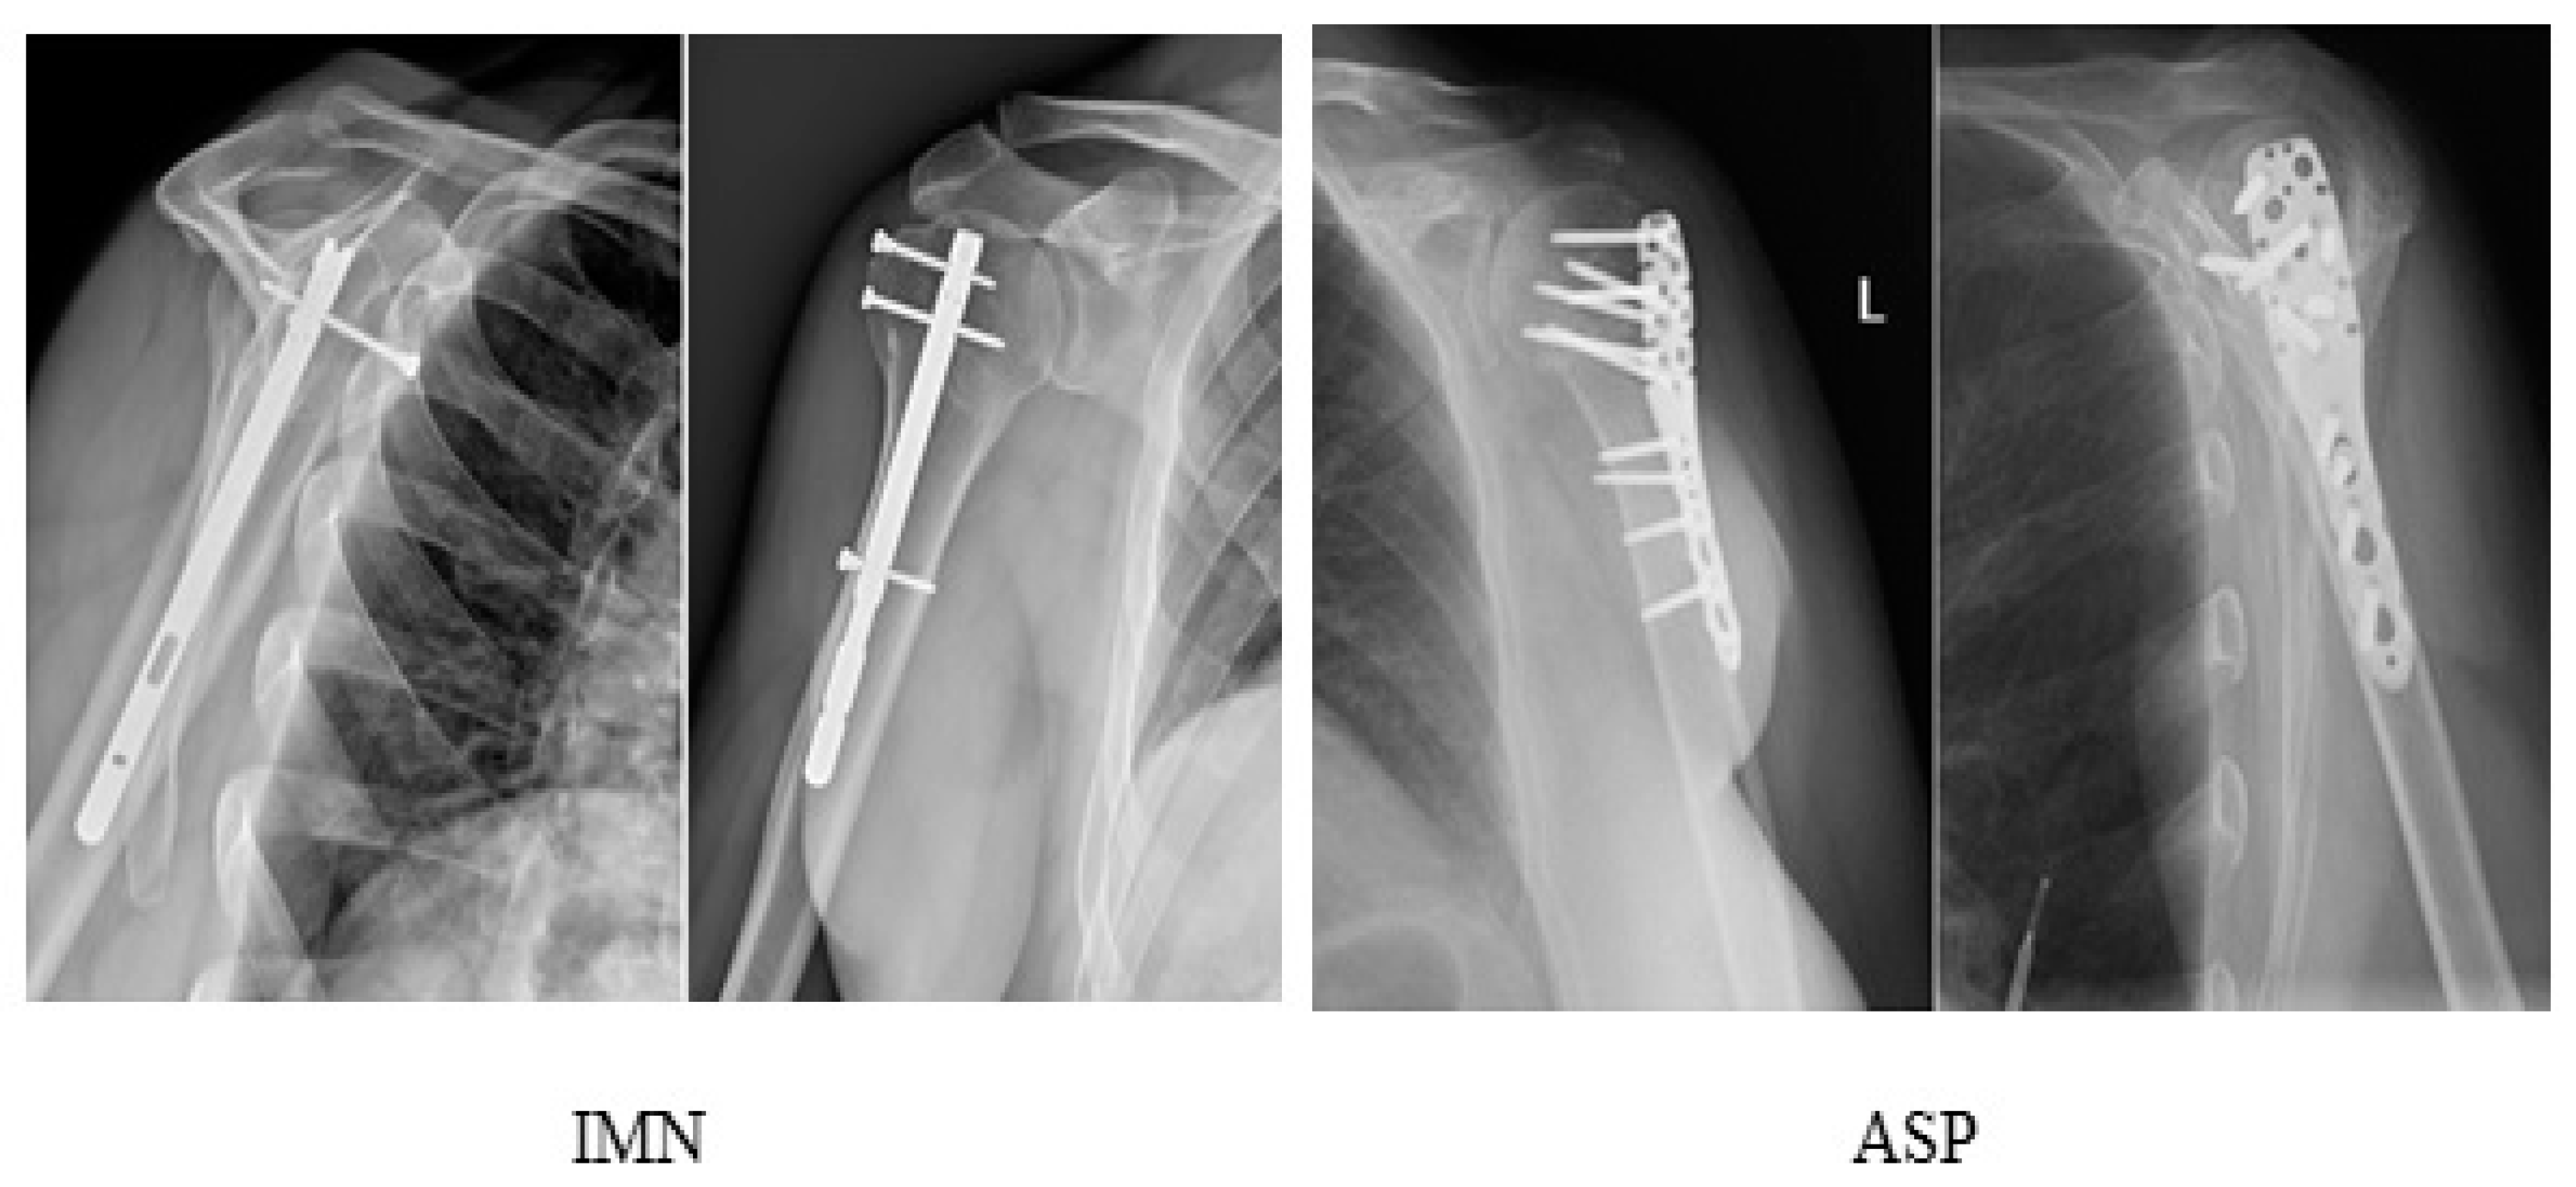

| IMN | 61/64 (95.3%) | 0 (0%) | 2 (3.1%) | 1 (1.6%) |

| ASP | 45/48 (93.8%) | 0 (0%) | 0 (0%) | 3 (6.2%) |